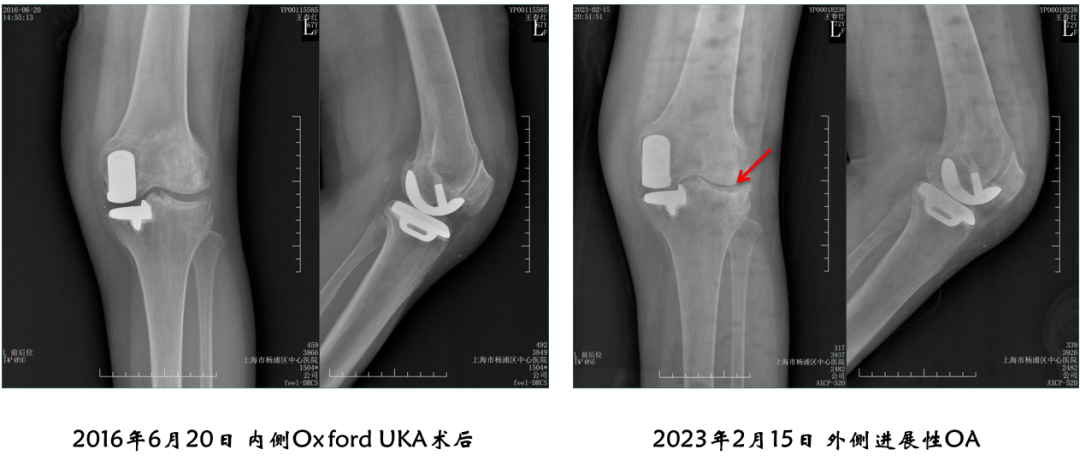

病例4:内侧OxfordUKA术后6.5年外侧进展性OA

病例4:Bi-UKA术后

病例4:Bi-UKA术后Bearing 后脱位的处理